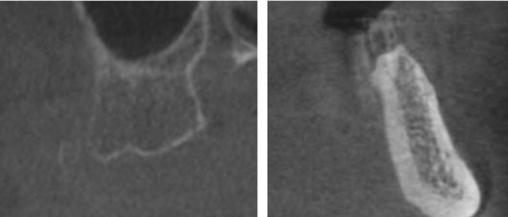

A recent 2025 retrospective review by Holtzclaw, et al.,11 evaluated anonymized cone beam computer tomography (CBCT) scans from 300 sequential referrals using PLACATE guidelines to determine transnasal dental implant feasibility. In this study, inferior conchae were initially located in the coronal plane, and imaging crosshairs were positioned just superior to this structure in the axial plane. To evaluate the ipsilateral and contralateral transnasal engagement points, imaging crosshairs were next positioned over each concha in the sagittal plane. This prelacrimal engagement point, sometimes referred to as the “Z-Point”,6,12 was then evaluated according to PLACATE guidelines as follows:

1. Simmen classification19 determined by measurement from the external aspect of the frontal maxilla to the most anterior aspect of the nasolacrimal canal (Figure 5)

2. Mediolateral measurement of prelacrimal bone width (Figure 6)

Figure 5 (left): CBCT slice (axial view) to determine Simmen classification.

Figure 6 (right): CBCT slice (axial view) for mediolateral measurement of prelacrimal bone width